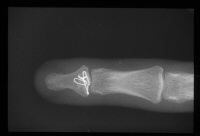

| Case 2. This patient sustained a closed displaced distal phalanx base fracture with dorsal-palmar split and dorsal subluxation of the larger fracture fragment. |

| This was managed with two wires - a cerclage wire, passed over the dorsum in a subperiosteal plane, and an interfragmentary palmar wire. The profundus tendon was found to have avulsed from the palmar fragment, and the tendon was reattached with sutures passed around the palmar component of the cerclage wire. A temporary longitudinal interfragmentary pin was also used (not shown). |